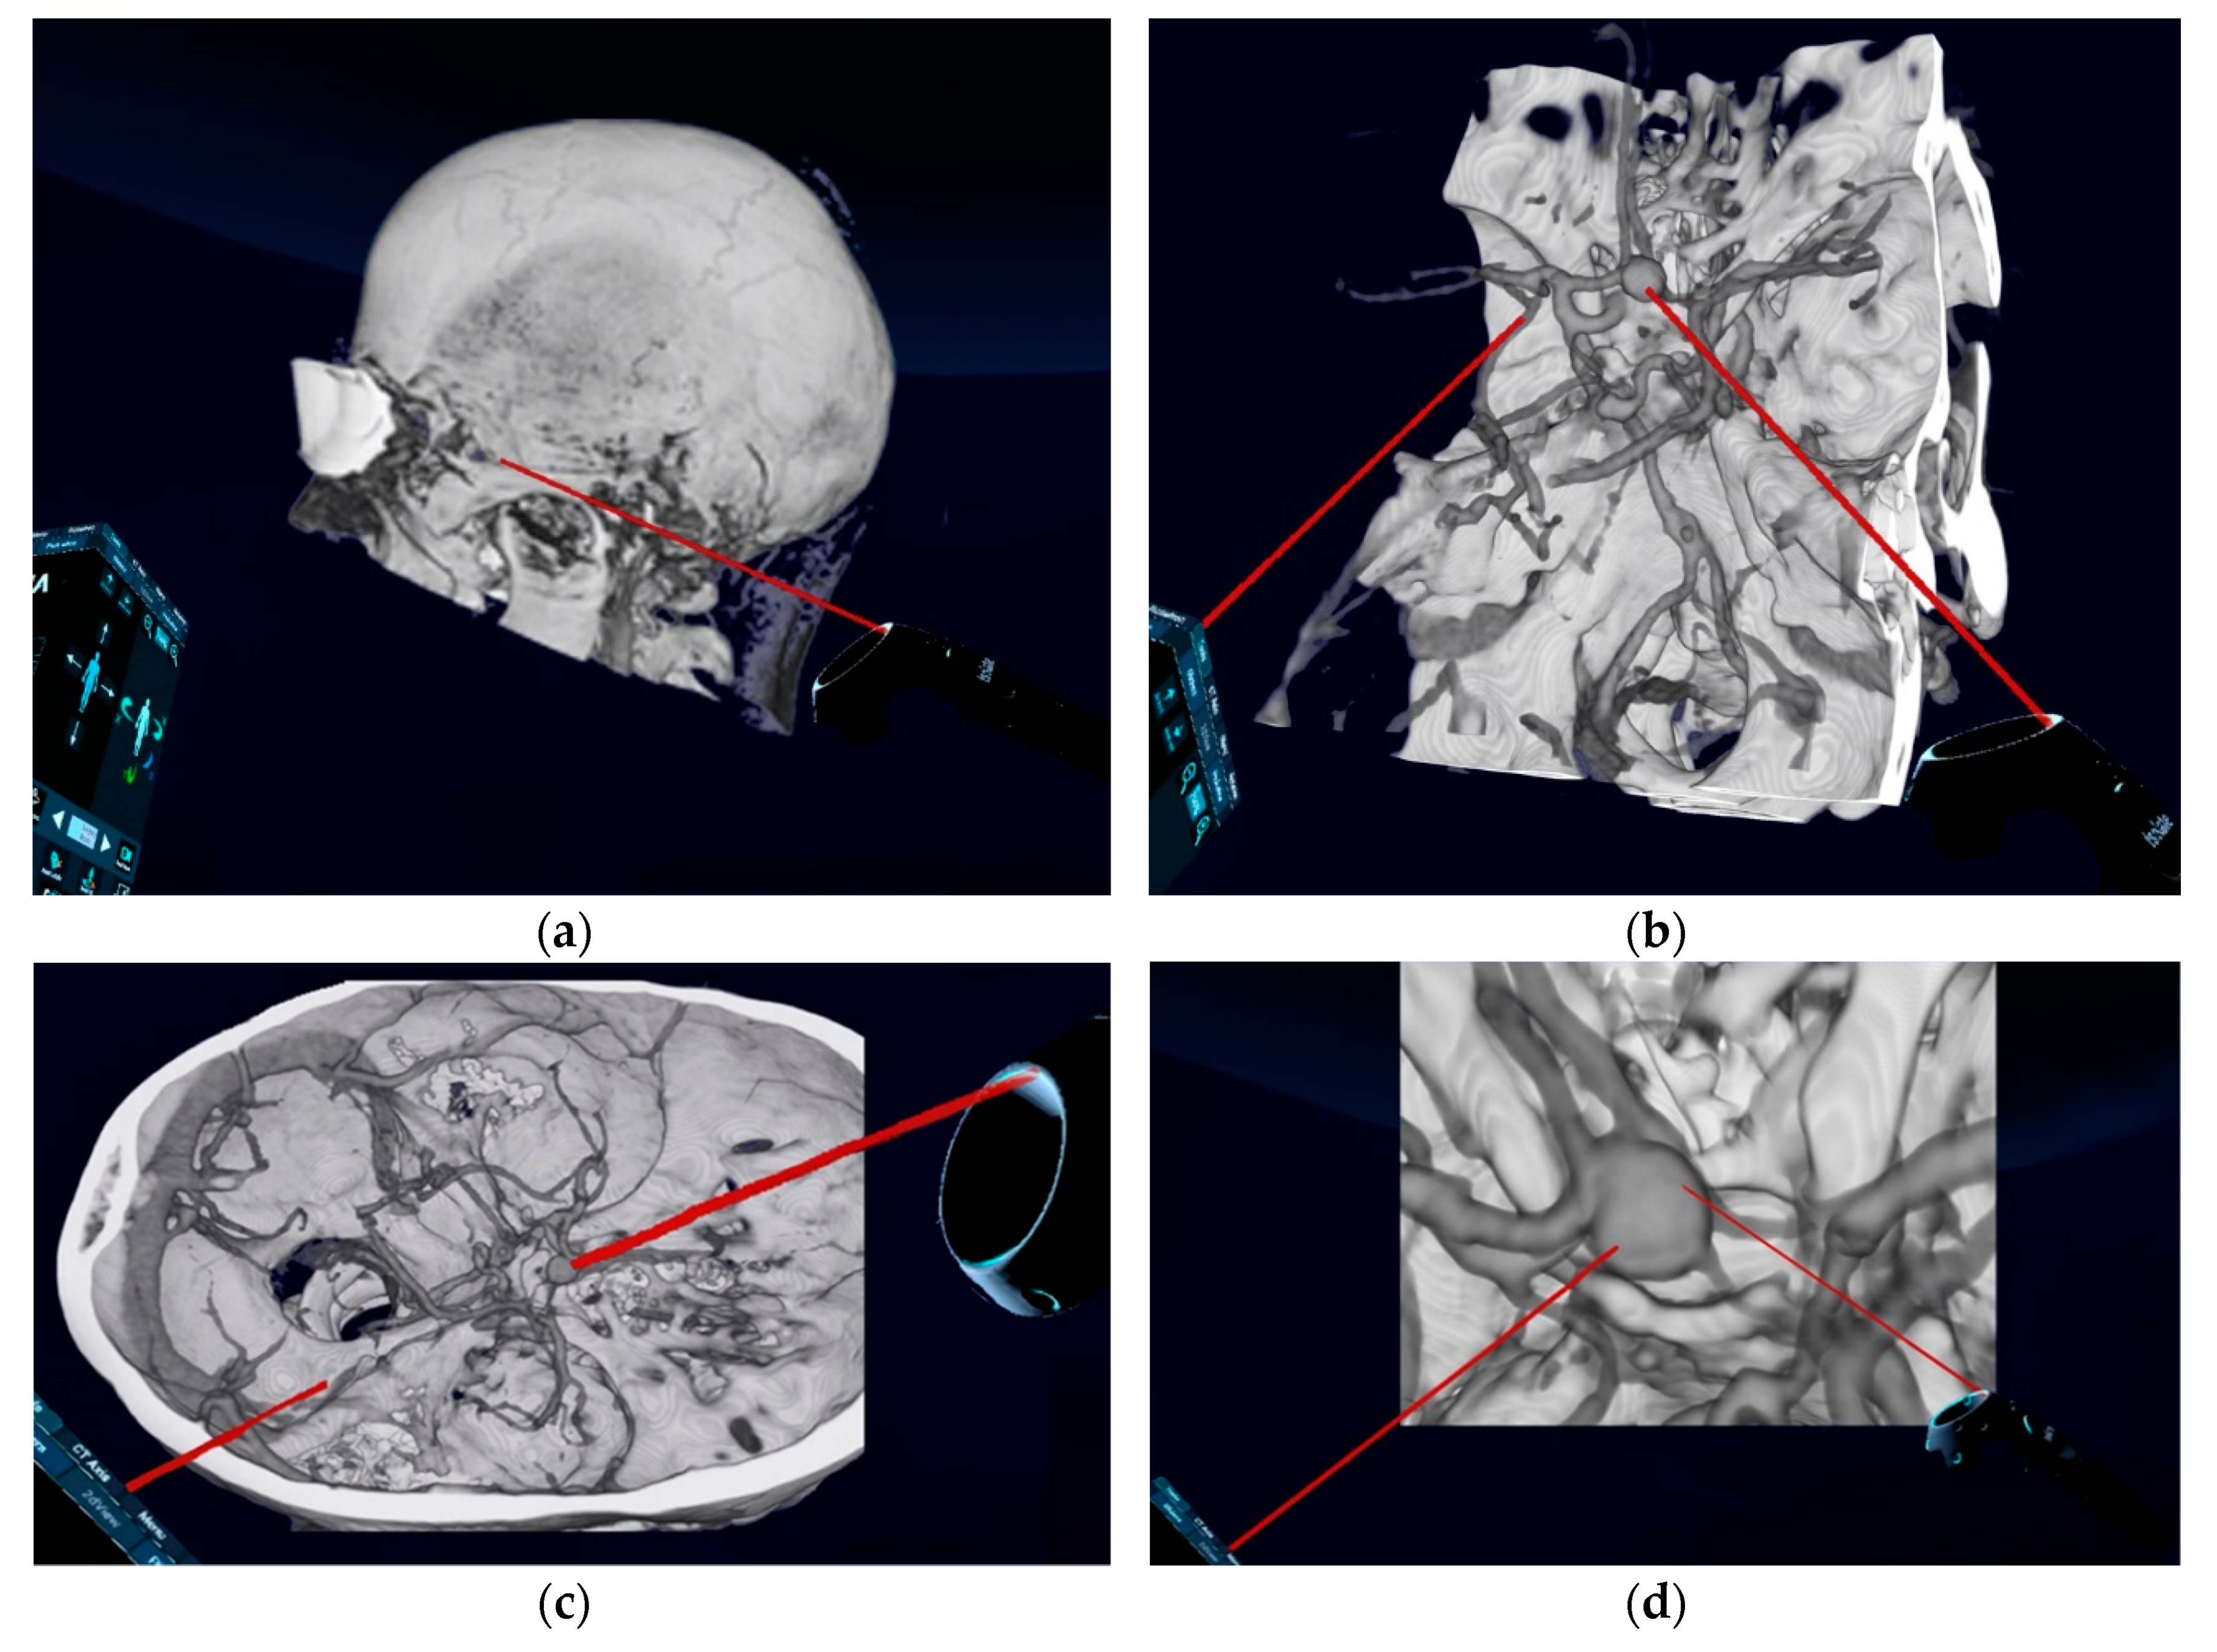

Conventional preoperative screen CTA scans (examples in Figure 2) of all included patients were retrospectively demonstrated to ten experienced, board-certified neurosurgeons who have at least 10-years-experience in vascular neurosurgery with at least 50 aneurysm clippings performed by each of them (to reduce any influence on the recommendations given and to avoid bias, neurosurgeons who performed the operations and who have done the reconstructions were excluded). They were asked to evaluate the identification of anatomical structures, as well as determine the preferred patient and head positioning, the surgical approach and approach side, and the clipping strategy using a questionnaire (Table 1). The reconstructed 3D-VR images (examples in Figure 3) of the same patients were retrospectively presented to the same neurosurgeons four weeks later, but in a different order to minimize the influence from the first questionnaire on the second. Again, the neurosurgeons were asked via the same questionnaire. To avoid influence from the patient- and disease-related data on the image evaluations, these data were not presented. The possible influence of the preoperative reconstructed 3D-VR images compared to the conventional preoperative CTA scans (2D and screen 3D) on detection of anatomical structures and on surgical planning and strategy was evaluated.

Figure 3.

Preoperative reconstructed 3D-virtual reality images of patients with unruptured ACoA aneurysm. (a) Lateral aspect of the skull; (b) oblique superior aspect of the aneurysm and relevant vascular anatomy and the skull base; (c) lateral superior aspect of the aneurysm and relevant vascular anatomy and the skull base; (d) zoomed superior aspect of aneurysm and relevant vascular anatomy. 3D, three-dimensional.